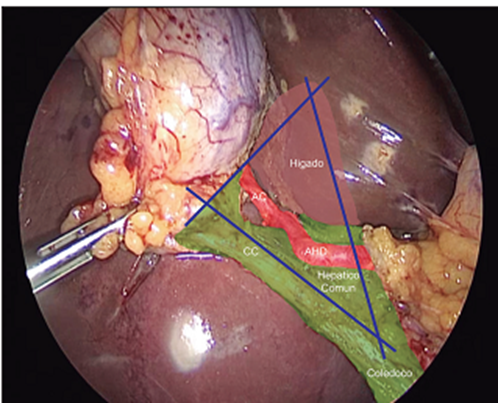

Tristructure method and identification of the Budde and Calot triangle: we must identify during LC: Cystic Duct (CC), common hepatic duct and common bile duct. Jean François Calot (1861-1944), French surgeon, his doctoral thesis was called “De la colecystectomy” and was completed in 1890; In it it describes an isosceles triangle given by the cystic artery and duct at its upper and lower limits respectively, and by the hepatic duct medially. International anatomical terminology contemplates the existence of this triangle under the term “cystohepatic trigone”. Calot insisted that "the surgeon must work by sight and not by faith." In 1906, Budde described an anatomical triangle between the CC, the hepatic duct and the liver, and called it the "bile duct triangle." It can be divided into triangle described by Budde (Figure 1) in two sectors, one medial (Critical Triangle) and another lateral (Safety Triangle), its separation limit being a line that goes from the hepatocystic angle, passing through the birth of the cystic artery and reaching the hepatic margin. The identification of the CT constitutes a universal method for safe cholecystectomy for both routes during a cholecystectomy present in the guidelines and score for the safety of this procedure. represented by the “cystic lymph node” or Mascagni node, which is always found lateral to the biliary tree and should form the medial end point of dissection.(3,6,7) Algieri et al.(5) agrees with the above. and they constitute principles of dissection during a cholecystectomy the Cuban school of surgery mentions in its work standards.

Figure1: Budde's triangle and its medial part that constitutes Calot's triangle are observed.

Visualization of the Sign of Lord Ganesha: This sign, also called the trunk or elephant head (Figure 3), is another measure to prevent this feared complication and this sign is part of the union of the infundibular technique and Strasberg's critical view. . Ashok et al.(17) in their study created a scoring system for safe cholecystectomy where the visualization of the sign of Lord Ganesha is part of it, granting 1 point when it is present, it constitutes one more tool in the arsenal for the prevention of injuries. of the bile duct. Tantia et al.(18) mention the visualization of the elephant trunk as an element to always take into account during a cholecystectomy and its non-visualization is associated with inability to adequately dissect Calot's triangle. Although this sign only contributes one point in this score, its non-visualization indicates an inadequate infundibular technique and critical safety vision, and may be associated with the possibility of an injury to the pathway without a change to an appropriate strategy. (19,20,21)

Figure 4: Rouviere's groove is observed, the green area shows the safe dissection plane.

Visualization of Rouviere's sulcus: Different anatomical landmarks for cholecystectomy have been described: among them, in 1924, Henri Rouvière, French surgeon, this sulcus measures 2 to 5 cm long and is present on the lower surface of the right lobe of the liver, running to the right of the hepatic hilum (Fig. 4). It is easily visible in the majority (80%) of cases in which it remains open (partially or completely), and usually contains the right portal pedicle and identifies the sagittal plane of the main bile duct. During LC, it is best seen when the neck of the gallbladder retracts into the umbilical fissure. The dissection can safely begin in a triangle anterior and superior to the plane of the sulcus. It is essential that the surgeon knows the safe dissection zone to delineate the cystic duct and cystic artery. Looking at the fixed anatomical landmark (B-SAFE) will help the surgeon identify and remain in the safe dissection zone. These fixed anatomical landmarks include the bile duct and base of segment 4 (B), Rouviere's groove and segment 4 (S), hepatic artery (A), umbilical fissure (F), and enteric viscera (E), p. duodenum, pylorus. The Rouviere sulcus can now be defined in three simple terms: a deep sulcus, a cleft, or a scar. It is recommended by Basukala et al.(22), Singh et al.(23), Cheruiyot et al.(24) and Al-Naser et al.(25) as the first step in laparoscopic cholecystectomy, the surgeon must look for this point reference (whether in the form of a scar, a cleft or an actual groove) that will be the plane of the main bile duct, and therefore avoid any dissection below this point to eliminate any danger to the bile duct during the surgery.(26,27)

Although the groove of Rouviere is increasingly mentioned as the first landmark to begin dissection during laparoscopic cholecystectomy to prevent bile duct injuries, the anatomy of the groove has not been described in clear and simple terms. With an increasing emphasis on patient safety in recent years, it is recommended to identify and follow some landmarks that can guide surgeons from where to start the dissection by identifying the common bile duct (CBD) plane even earlier. before the dissection begins. A common landmark or landmark that is increasingly described in recent reports is the Rouviere groove. This sulcus, which was barely seen and described in the era of open surgery, is seen very clearly during LC. Today the SR is an element present in the guidelines proposed by Wakabayashi et al.(2), Gupta et al.(8) and Barauskas et al.(19) in favor of a safe cholecystectomy, this dissection plane should never be violated which promotes adequate visualization of the SVC, thus achieving a safe procedure.